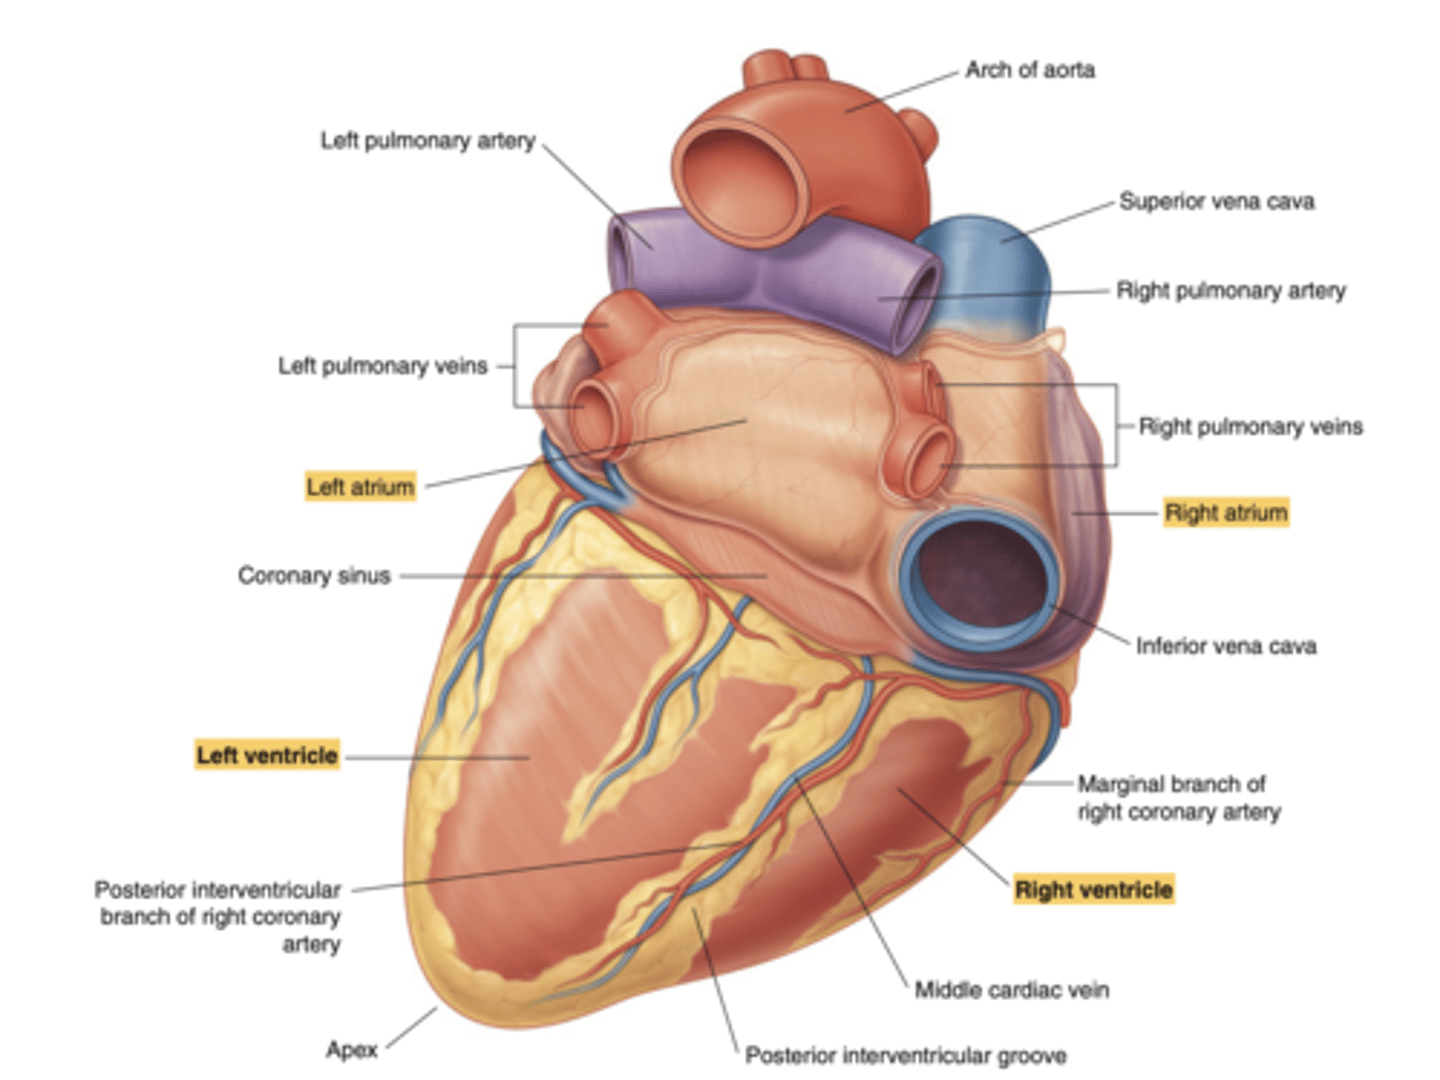

Show the position of the coronary sinus in the posterior view of the heart and its function

collects deoxygenated blood from most of the heart's venous system

delivers it to the right atrium for reoxygenation.

Show the position of the ventricles and auricles in the posterior view

Which veins enter the left atrium?

left pulmonary veins

right pulmonary veins

ALLOWS OXIGENATED BLOOD FROM THE LUNGS TO ENTER THE HEART